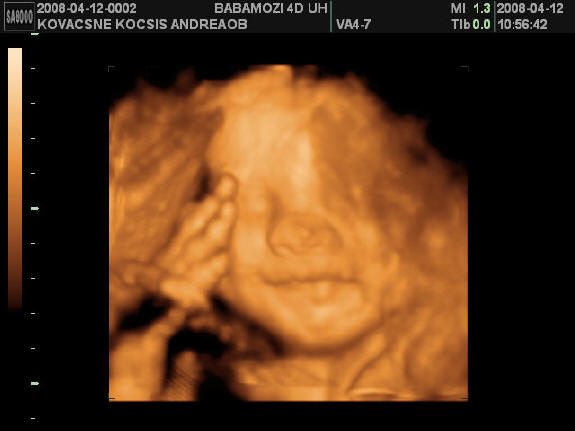

[quote="mpatr"][ írta:mpatrb]Nici, a felvétel élessége és sikerültsége sok mindentől függ.

A profi gépen túl a profi és türelmes szonográfus, a lepény és baba helyzete (mellső fali lepénynél kicsit nehezebb az ügy, meg a babák is imádnak belebújkálni a lepénybe), a magzatvíz mennyisége, a mama hasfalának zsírrétege (mennyire dagi anyuci) szóval ezek (biztos van még) min-mind befolyásolják a felvétel minőségét.

Nekem sikerült ugyanarról a gyerkőcről aki a pocimban van nagyon tuti és nagyon sz..r képet is készíteni ugyanazzal a géppel.

Érdemes többször próbálkozni.